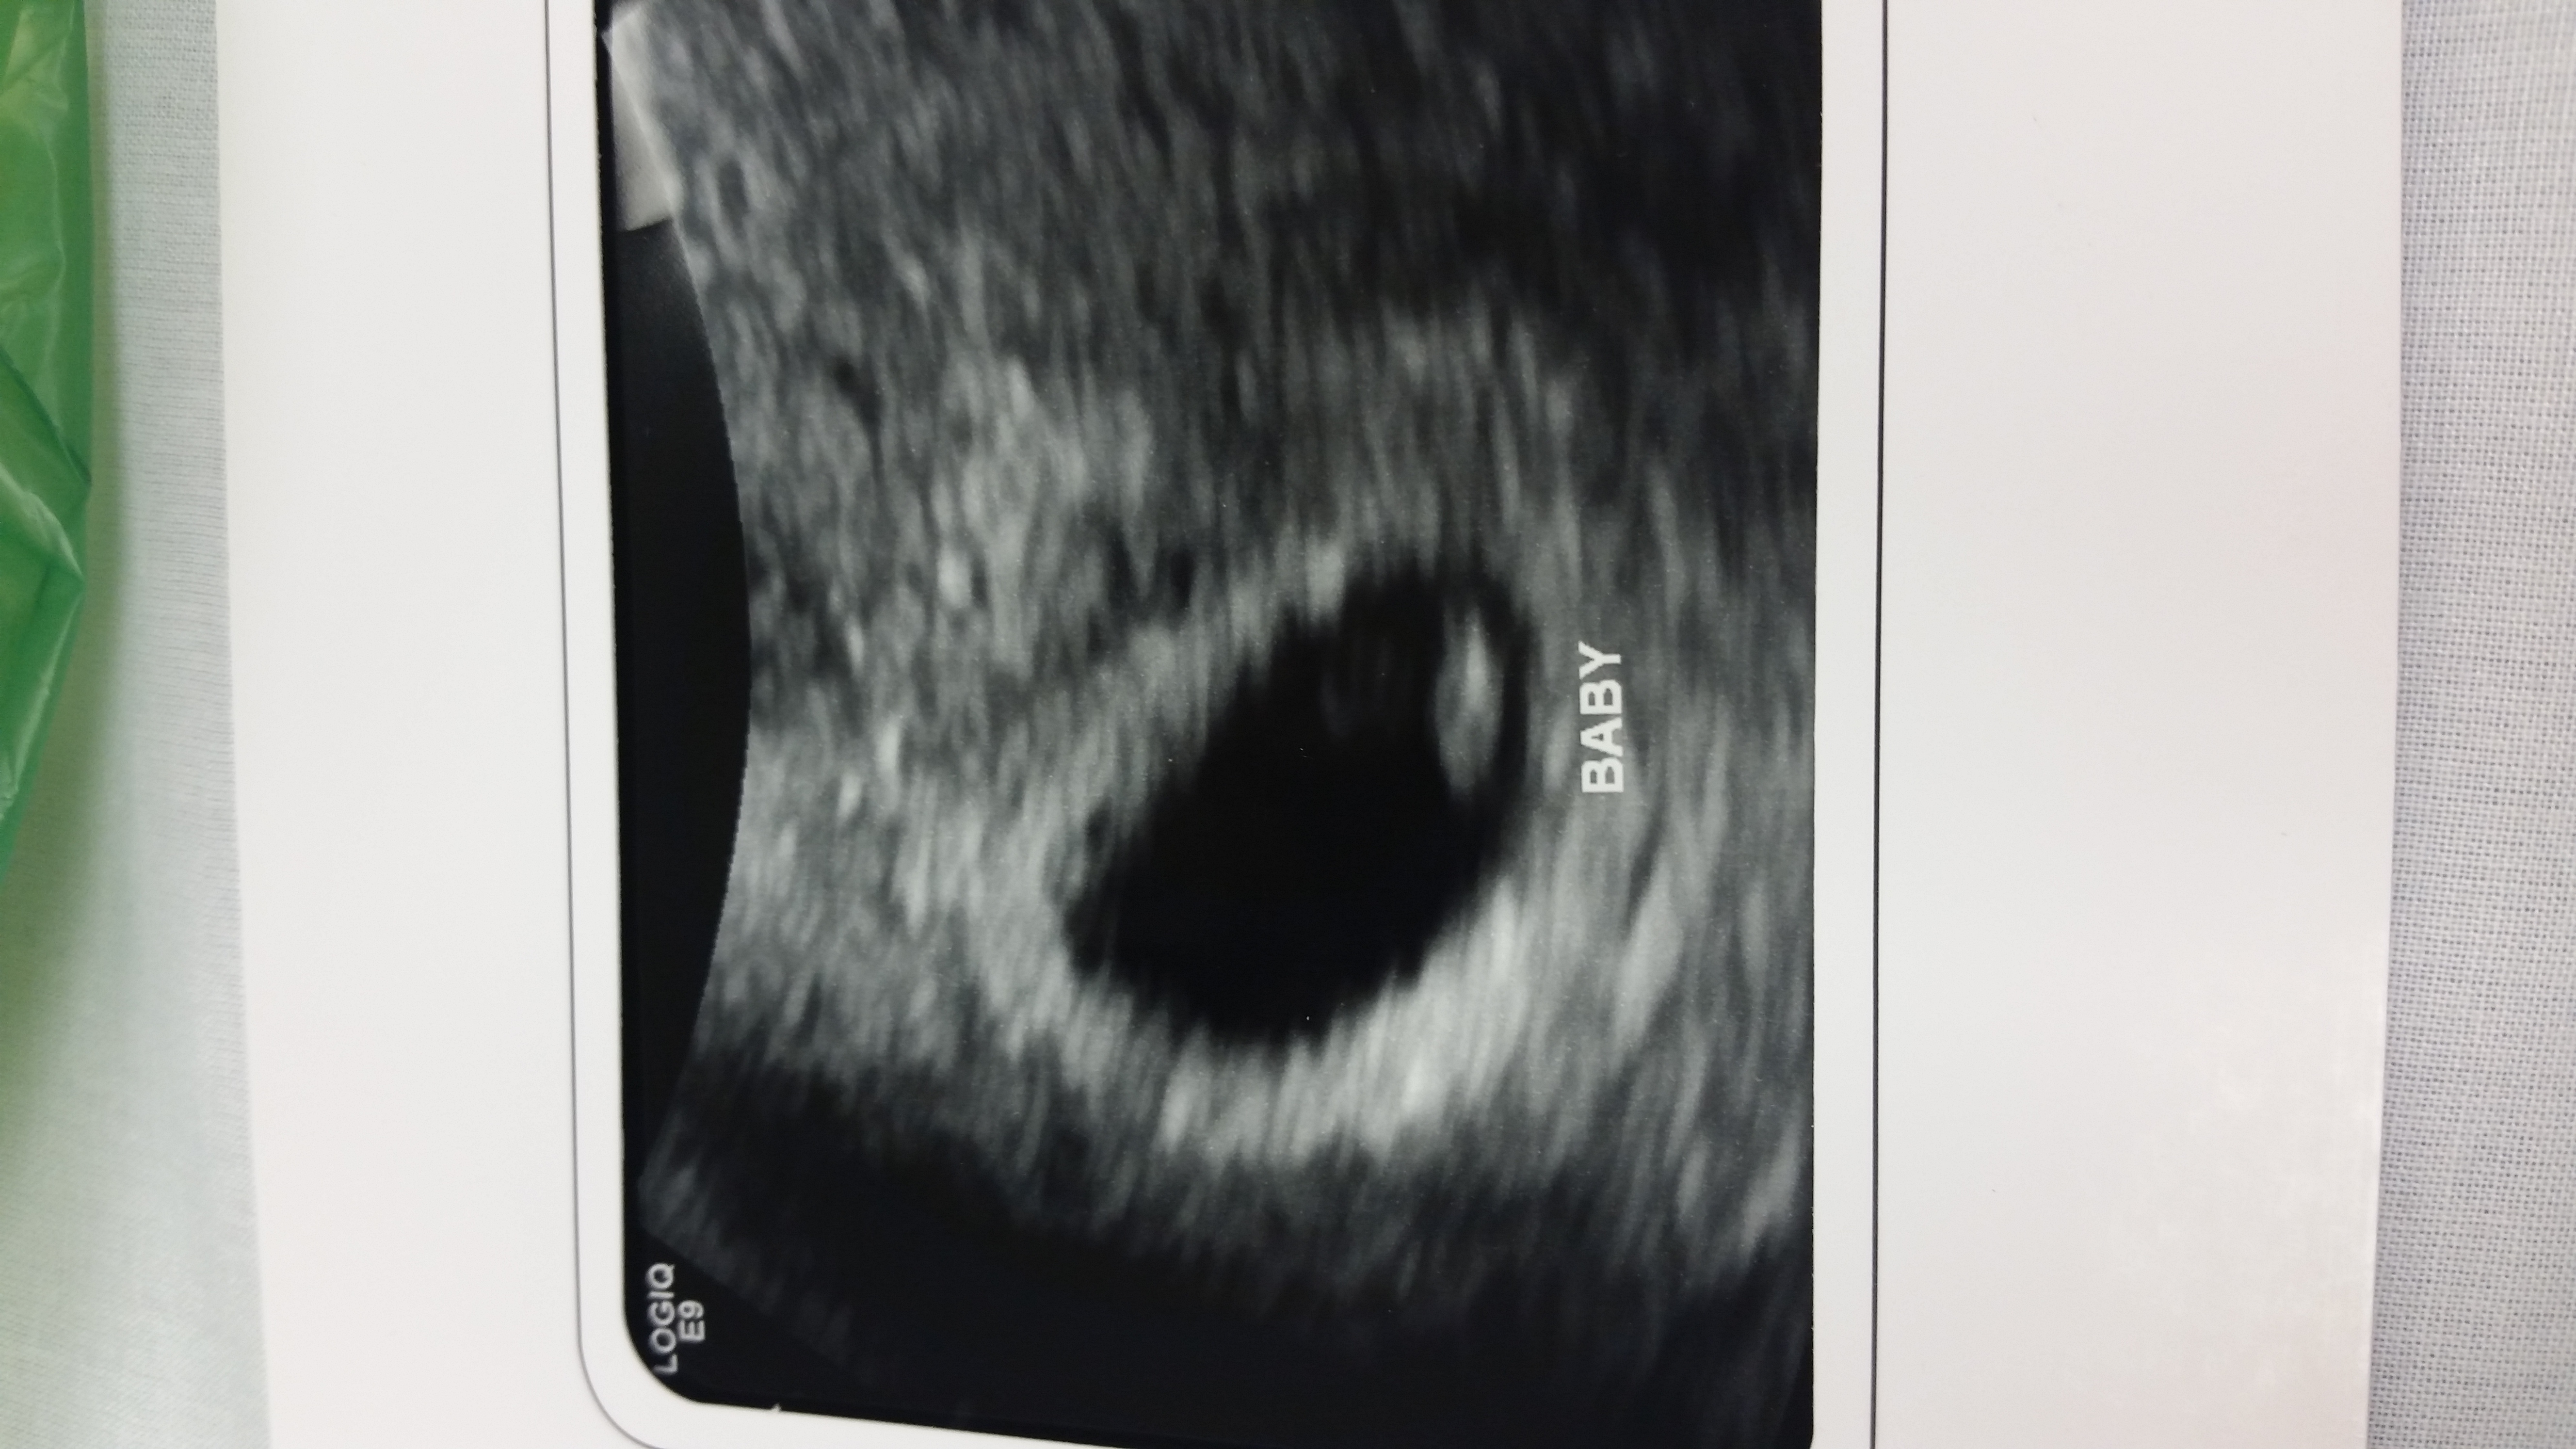

Fast forward to yesterday, my first ob appt this pregnancy. We did an ultrasound and they said baby is measuring 6w6d and heartbeat was 158. Baby looked much different but still, only 5 'days' of growth over a week and a half? I'm worried, doc is not, they just moved my edd to what baby is measuring now. According to my current due date, I would have been 3w2d when I found out and that just seems crazy.

Attached u/s first from 10/20 then from 10/30